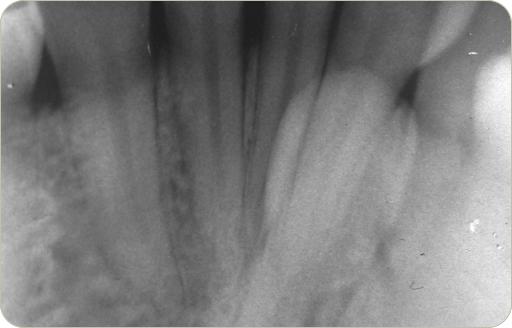

Especialistas en Medicina y Patología Bucal 2010

3